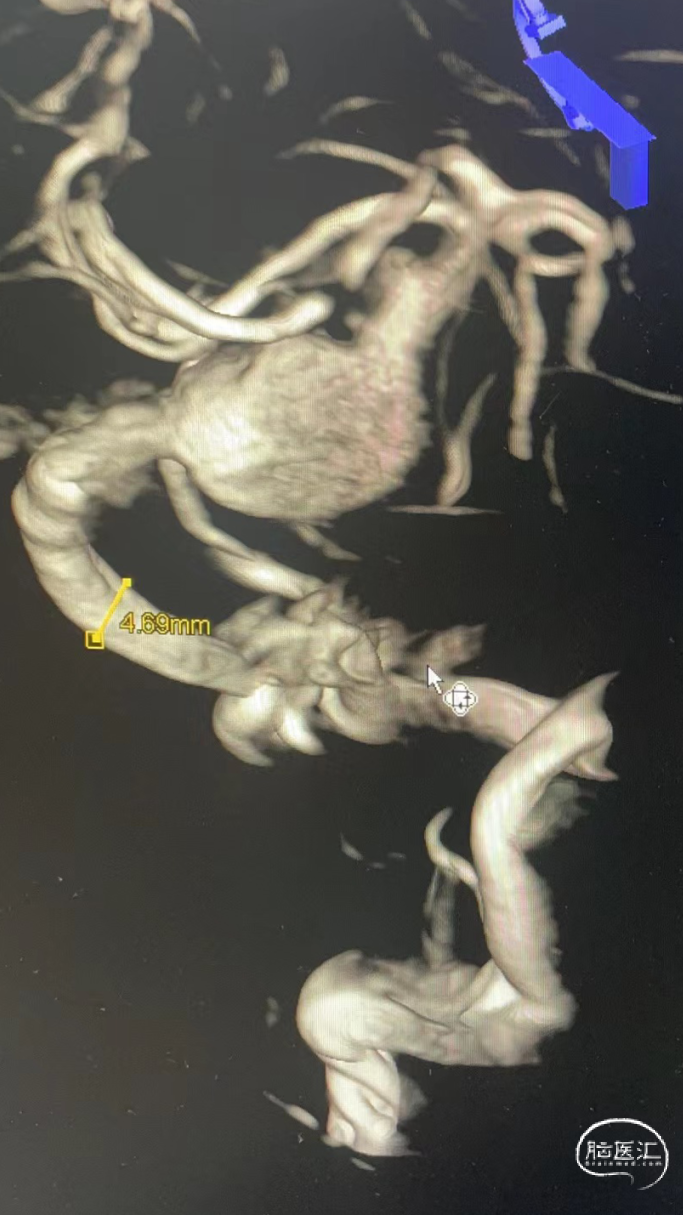

术前影像资料

术前测量:

覆盖长度:37mm

动脉瘤内有血栓,部分不显影。

直径:

瘤颈远端:3.83mm

瘤颈近端:4.71mm

近端锚定点:3.73mm

选择Lattice血流导向密网支架

5.3mm*37mm,8个球囊